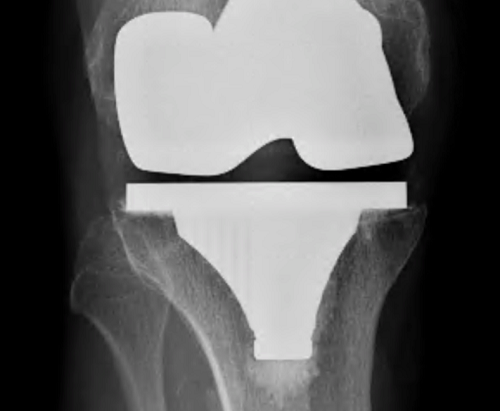

Patella resurfacing is a procedure that is frequently performed during knee replacement surgery to remove the undersurface of the kneecap and replace it with a plastic surface. Patellar resurfacing is inconsistently used in primary total knee replacements, according to current clinical practice.

The patella is resurfaced when the cartilage and bone along its back are shaved and smoothed. The area is then covered with an implant, which can be made of metallic, polyethylene (plastic), or a combination of the two. Many surgeons choose all-polyethylene backing since studies indicate that it is associated with fewer issues.